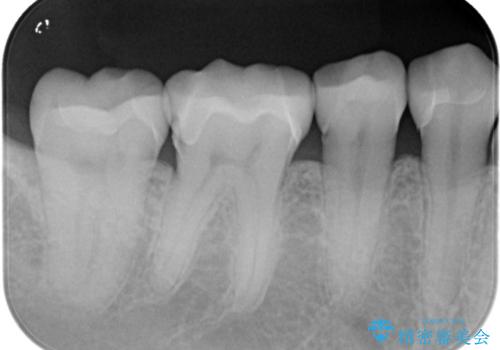

- 主訴:下の歯に入っている銀歯が笑うと目立つので白くしたい。

下顎臼歯部に入っている保険適用のメタルインレー(4箇所)を、審美性・適合性・清掃性の良いセラミックインレーにてやり替えました。